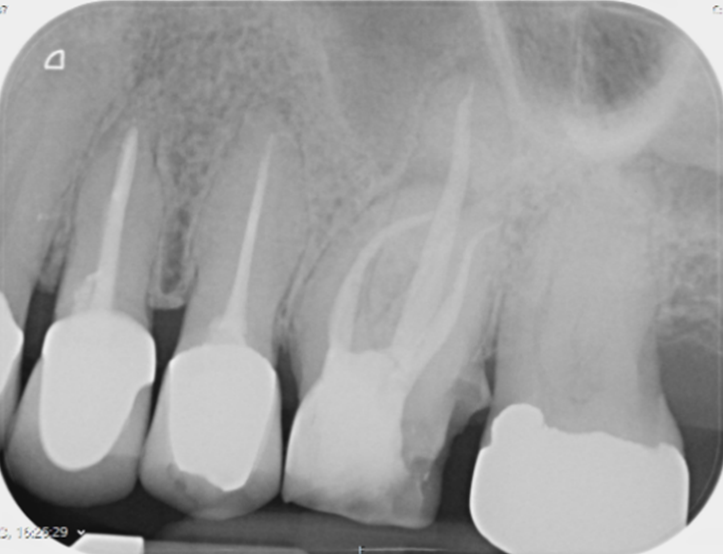

Pre-operative X-ray

Post-operative X-ray